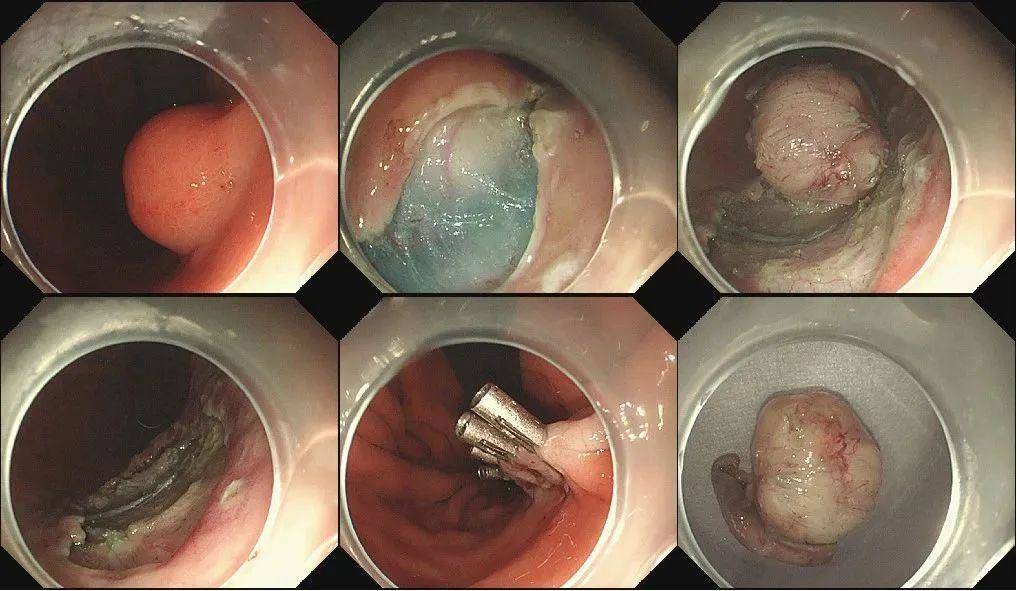

1月7日上午,潘晓林主任对周女士胃内肿瘤实施了内镜黏膜下剥离术(ESD),不到30分钟就顺利切下直径约2.0cm的肿瘤,术中没有出血和穿孔,术后用钛夹牢固缝合创面。

在术后禁食2天,第4天就顺利出院,目前恢复良好。术后病理提示(胃体)符合胃肠间质瘤,极低危组。根据病理结果,肿瘤完全切除干净,同时没有恶变。将结果反馈给周女士,周女士这才安下心来,同时也庆幸自己选择了内镜下切除。

图2 患者周某ESD切除胃间质瘤过程